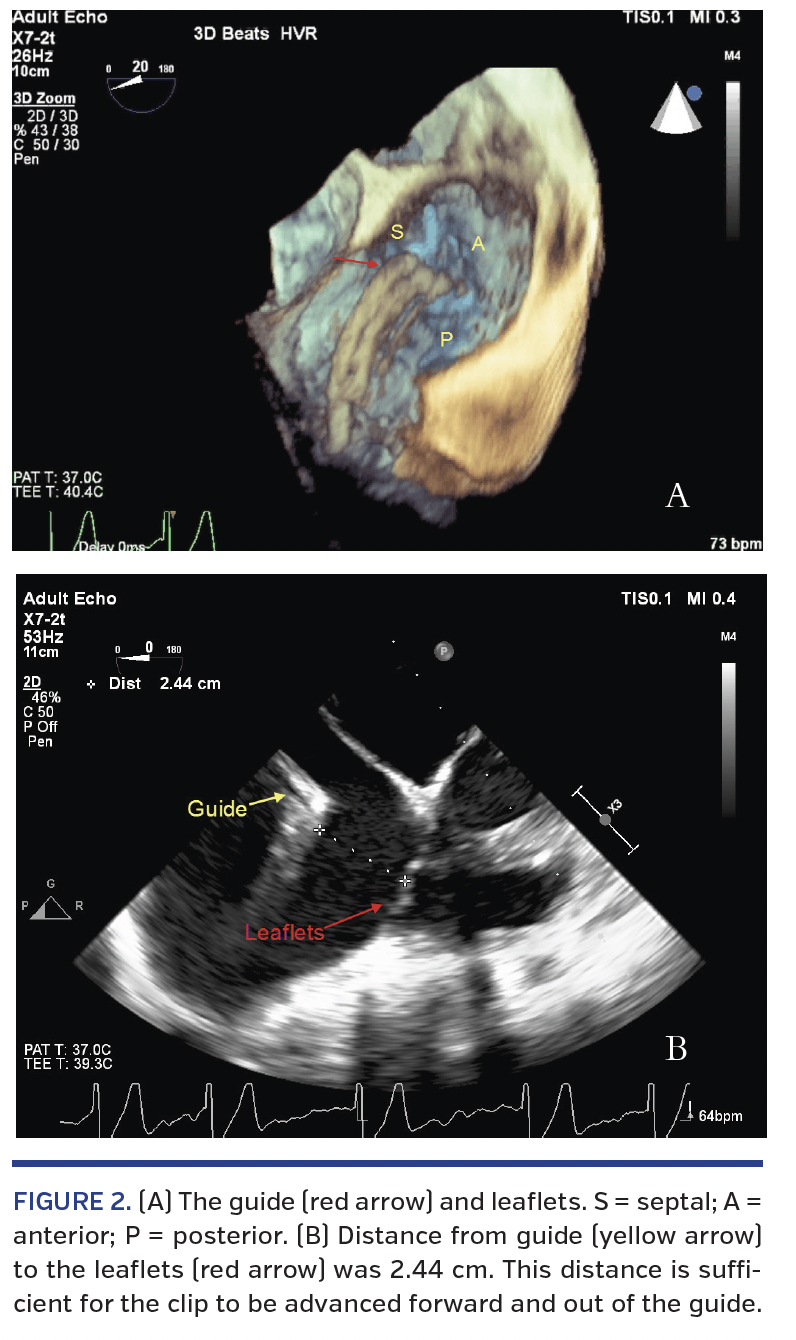

The guide was then positioned using a three-dimensional view from the right atrial perspective, followed by a four-chamber view to show distance from the leaflets (Figure 2). These views indicated there was enough space to advance a clip safely above the leaflets. A clip was then brought outside the guide and opened, followed by rotation to be perpendicular to the chosen coaptation plane (Figure 3). As our goal was to clip the tricuspid valve anterior-septal leaflet coaptation, the mid-esophageal four-chamber TEE view was used. We noted that the guide catheter elbow was abutting against the interatrial septum, termed “septal hugger,” which we corrected in order to make the clip approach perpendicular to the tricuspid valve leaflets (Figure 4). We used a combination of lateral movement of the guide, clockwise or counterclockwise guide catheter

rotation to translate anterior or posterior torque, and use of the device’s anterior-posterior (A/P) and +/- rotating knobs in order to achieve optimal clip position and coaxial approach to the intended valve coaptation plane. We then crossed the tricuspid valve leaflets, assessed again for clip perpendicularity in the TEE subgastric view, and grasped in the mid-esophageal four-chamber TEE view. Leaflet grasp was then evaluated and found to be adequate (Figure 4). As per the accepted standard operating procedures for MitraClip use, we also utilized adjunctive simultaneous fluoroscopy throughout the procedure to ensure appropriate gross directionality of the equipment and to visualize clip opening and closing during grasp preparation.

In this paper, we describe a periprocedural imaging algorithm to facilitate grasping the leaflets of the tricuspid valve using a MitraClip device (Table 1). From an echocardiographic standpoint, the evaluation begins with three-dimensional TEE imaging to understand initial maneuvering to the correct leaflet pair and gross rotation for perpendicularity. The TEE transgastric view is then obtained to evaluate clip position along the commissural-central axis, with use of the “x-plane” to add to the ability to understand perpendicularity. After this, an appropriate two-dimensional view allows fine-tuning of rotation, including correction of a septal hugger guide catheter, as described above in Figure 4. Adjunctive fluoroscopic imaging can be used to show how subsequent clips can relate to the first marker clip location and position. The LAO and AP-RAO views show the clips in two different directions, which can facilitate guide positioning before clip advancement and provide assistance when TEE image acquisition is challenging.